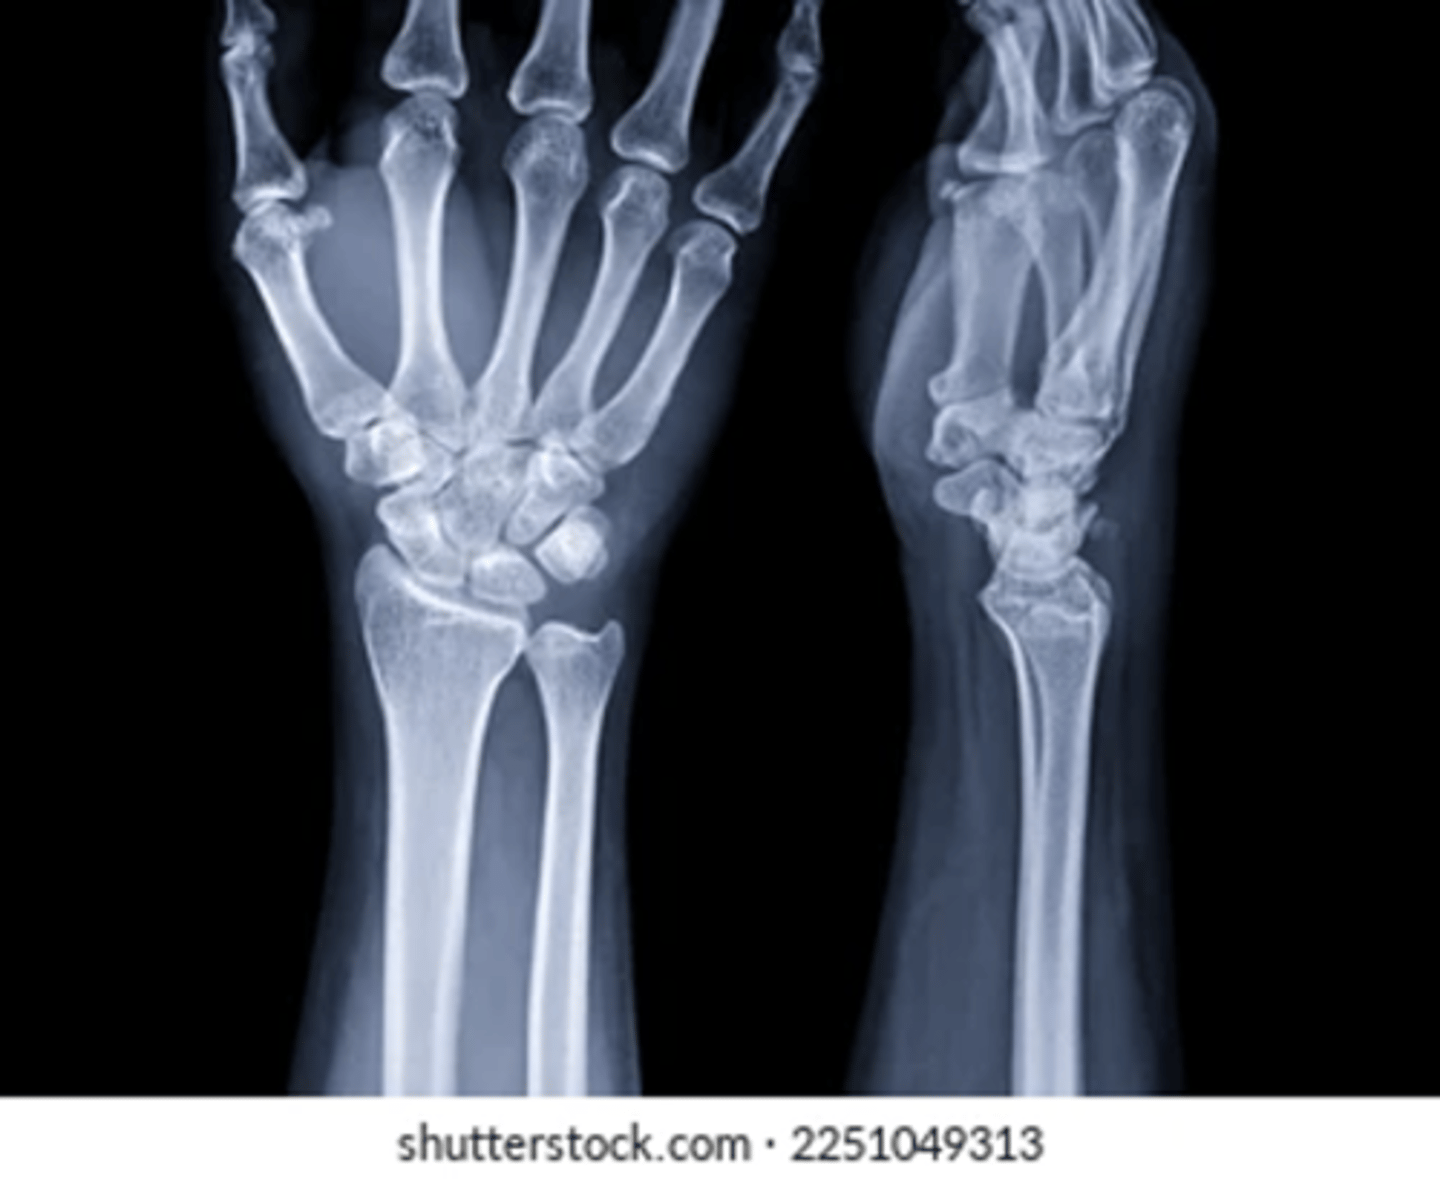

what is this

fall on outstretched hand

FOOSH

describe

no fracture